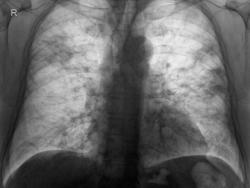

Пациент поступил ещё 19.11.09г. с жалобами на надсадный сухой кашель, повышение Т до 39,5 С, заложеность носа, одышку смешанного характера при незначительной физ. нагрузке, боли в суставах , миалгии. Сразу были сделаны снимочки и на следующий день:

Диагноз был выставлен: Острое респираторно вирусное заболевание: острый назофарингит, острый ларинготрахеит. Осложнение: двухсторонняя пневмония.

Сегодня сделали контроль:

Хоть по данной рентген-картине динамика отрицательная, однако пациента температура тела не беспокоит. Данный случай решил продемострировать в продолжение предыдущего, всё же считаю пневмония вирусной этиологии, но как видно течение разное.

Если вспомнить, чему нас учил Розенштраух, то на вирусную пневмонию не очень похоже. Вирусные больше с интерстициальным компонентом. А здесь мы имеем по всем легочным полям множество фокусов инфильтрации легочной ткани (паренхиматозный компонент), различных размеров, плотности, сливающихся между собой. Есть такой термин "терапевтический сепсис". Очень похоже. При этом отсутствие положительной динамики за 10 дней неспецифической терапии. Ну никак не вирус. И проявил бы настороженность к tbc.

Соглашусь с Владимиром Васильевичем - мало походит скиалогически на "вирусную пневмонию". При вирусной пневмонии, действительно" интерстициальная компонента довольно выражена.

Динамика весьма "не утешительнавя" и не прогнозируемая, с учетом проведенного лечения, не исключается "септический процесс", да и казеозная так весьма может начинаться, а позможно уже и началась.

И не будь "первого снимка", весьма можно было-бы и о метастазах подумать. Весьма значительное количество крупных "фокусных" теней, да еще и неоднородной структуры.

Весьма значительное количество крупных "фокусных" теней, да еще и неоднородной структуры.

Да и "полости", пусть мелкие, уже наличествуют. На мой взгляд, весьма серьёзно надо "раскатать" мокроту.

Поддержу мнение автора демонстрации, с учётом клиники и R-картины больше данных (ИМХО кончно) за пневмонию вирусной этиолгии( это особенно хоршо видно на последней R-грамме-выраженный интерстициальный компонент).Как правильно отметила Татьяна Валентиновна, к вирусной инфекции, часто присоединяеться бактериальная( инфльтрацию, что мы видим, вероятно надо расценивать, как проявления пневмонии бактериального происхождения). Кстати, для вирусной пневмонии совсем нехарактерно быстрое разрешение, скорее наоборот, затяжное течение( которое может быть и при бактериальной пневмонии, даже без сочетания с вирусной инфкецией). Данные за туберкулёз и метастатическое поражение, на мой взляд неубедительные.

Присоединяясь, коллеги, к вашей очень увлекательной дискусси, хочу заметить, что процесс диссеминированный, двусторонний, неравномерный и к тому же несимметричный, в итоге: в острый диссеминированный туберкулёз едва ли укладывается, больше данных при остром развитии клиники всё же за острую пневмонию, может вначале заболевания и вирусную, с дальнейшим присоединением бактериальной флоры, но клинические данные скудно изложены, поэтому помня заповедь "ни шагу без клиники", надо видеть пациента, чтоб принимать окончательное решение

Подтверждение свиного гриппа методом ПЦР.

Дело не такое простое оказалось, а расценил первоначальную картину как тотальное изменение с обеих сторон, но мои коллеги в описании указали "субтотальное " а значит пневмония субтотальная. А последнем контроле. который я описывал, я остался при своём, изменения идут тотальные да и ещё со СЛАБО ОТРИЦАТЕЛЬНОЙ ДИНАМИКОЙ, видимой я зацепил наших уважаемых клиницистов, они видимо на это дело пожаловались моей заведующей, она уже них просто пошла на "поводу" и описала "контрольное орисание" в котором указала "субтотальную пневмонию, смешенной этиологии, в ст. разрешение? "Вот такое вот полное не годование моё :-( "глухо как в танке"

А пациент лечиться у нас в клинике, окружного статуса. И дело в том что ни каких изменений по поводу даже присоединение вторичной какой либо инфекции, в ОАК, нет. Кровь чистая, возможно там есть лимфоцитоз но он минимальный